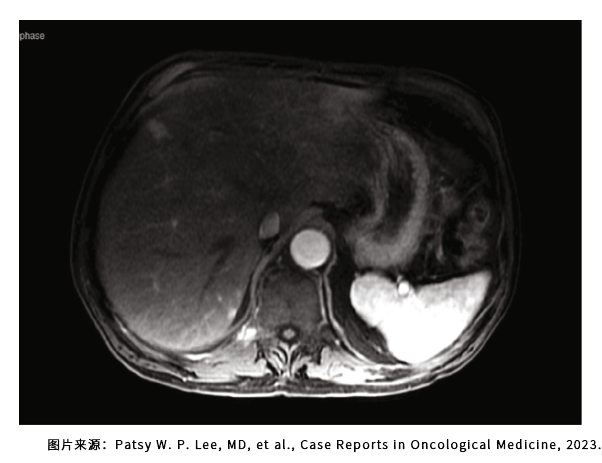

对比增强CT的检查显示胰管和胆总管扩张,胰周淋巴结轻度肿大,核磁则发现胰管内存在边界不清的病变病灶,通过细针活检显示为肿瘤细胞,这个患者在2019年10月接受了手术,病理显示为胰头1级、5.1厘米的腺癌,肿瘤累及淋巴结。2个月后患者开始使用术后辅助化疗之前的检查发现,肝脏有转移灶,门静脉的淋巴结也是阳性,也就是整个手术过程受罪但是没切除干净。

三线治疗之前肝脏的病灶情况